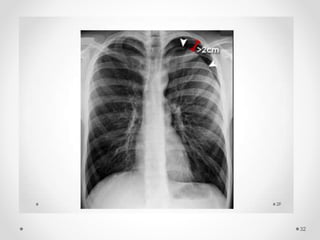

Quantification of the size

The simple method to estimate the size

Small, a visible rim of < 2 cm between the lung margin and the chest wall

Large, a visible rim of ≥2 cm between the lung margin and chest wall

 A pneumothorax of 2 cm on the PA chest

radiograph occupies about 49% of the

hemithorax volume

 Lung is 8 cm, hemithorax is 10 cm in diameter

 Equation

Volume of pneumothorax = (HT3 – L3) ÷ HT3

= (103 – 83) ÷ 103

= (1000 – 512) ÷1000

= 0.49